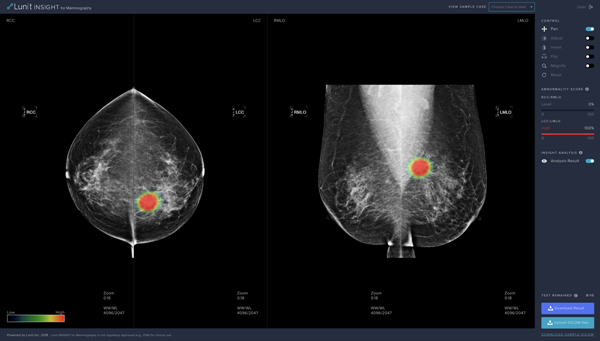

루닛의 신제품인 유방촬영술을 위한 루닛 인사이트는 97%의 정확도로 유방암을 발견하는 의료 인공지능 소프트웨어다.

촬영된 영상 이미지를 업로드하면 종양의 위치는 히트맵으로, 종양의 악성 정도는 점수로 각각 표기된다.